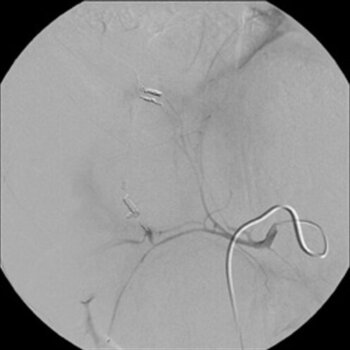

Digitale Subtraktionsangiografie: Nach Spiralembolisation mehrerer Subsegmentäste der A. hepatica stehen die zahlreichen Blutungen.